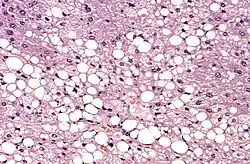

Corte histológico

Una sección histológica o corte histológico es una sección o rodaja fina de un tejido biológico adherida sobre un portaobjetos y generalmente coloreada con alguna tinción específica para resaltar una parte de la estructura.[1] Por lo general, se cortan con un micrótomo con un espesor de unos 0,5 a 10 micras, aunque lo más común es que sean de 3 a 6 micras, porque deben ser atravesados por la luz para que puedan ser observados bajo un microscopio.[2] Se emplean con frecuencia en los laboratorios de histología y de anatomía patológica.

El método de tinción de rutina es el denominado como hematoxilina-eosina (H-E). La hematoxilina es un colorante nuclear, y la eosina, citoplasmático. También existen las denominadas técnicas especiales, tal como: Gomori (para fibras de reticulina), Ziehl Neelsen (para bacilos ácido-alcohol resistentes), Grocott (para hongos), orceína (para fibras elásticas), Gordon-Sweet, rojo Sudán, negro Sudán, azul de Nilo, Golgi, etc.